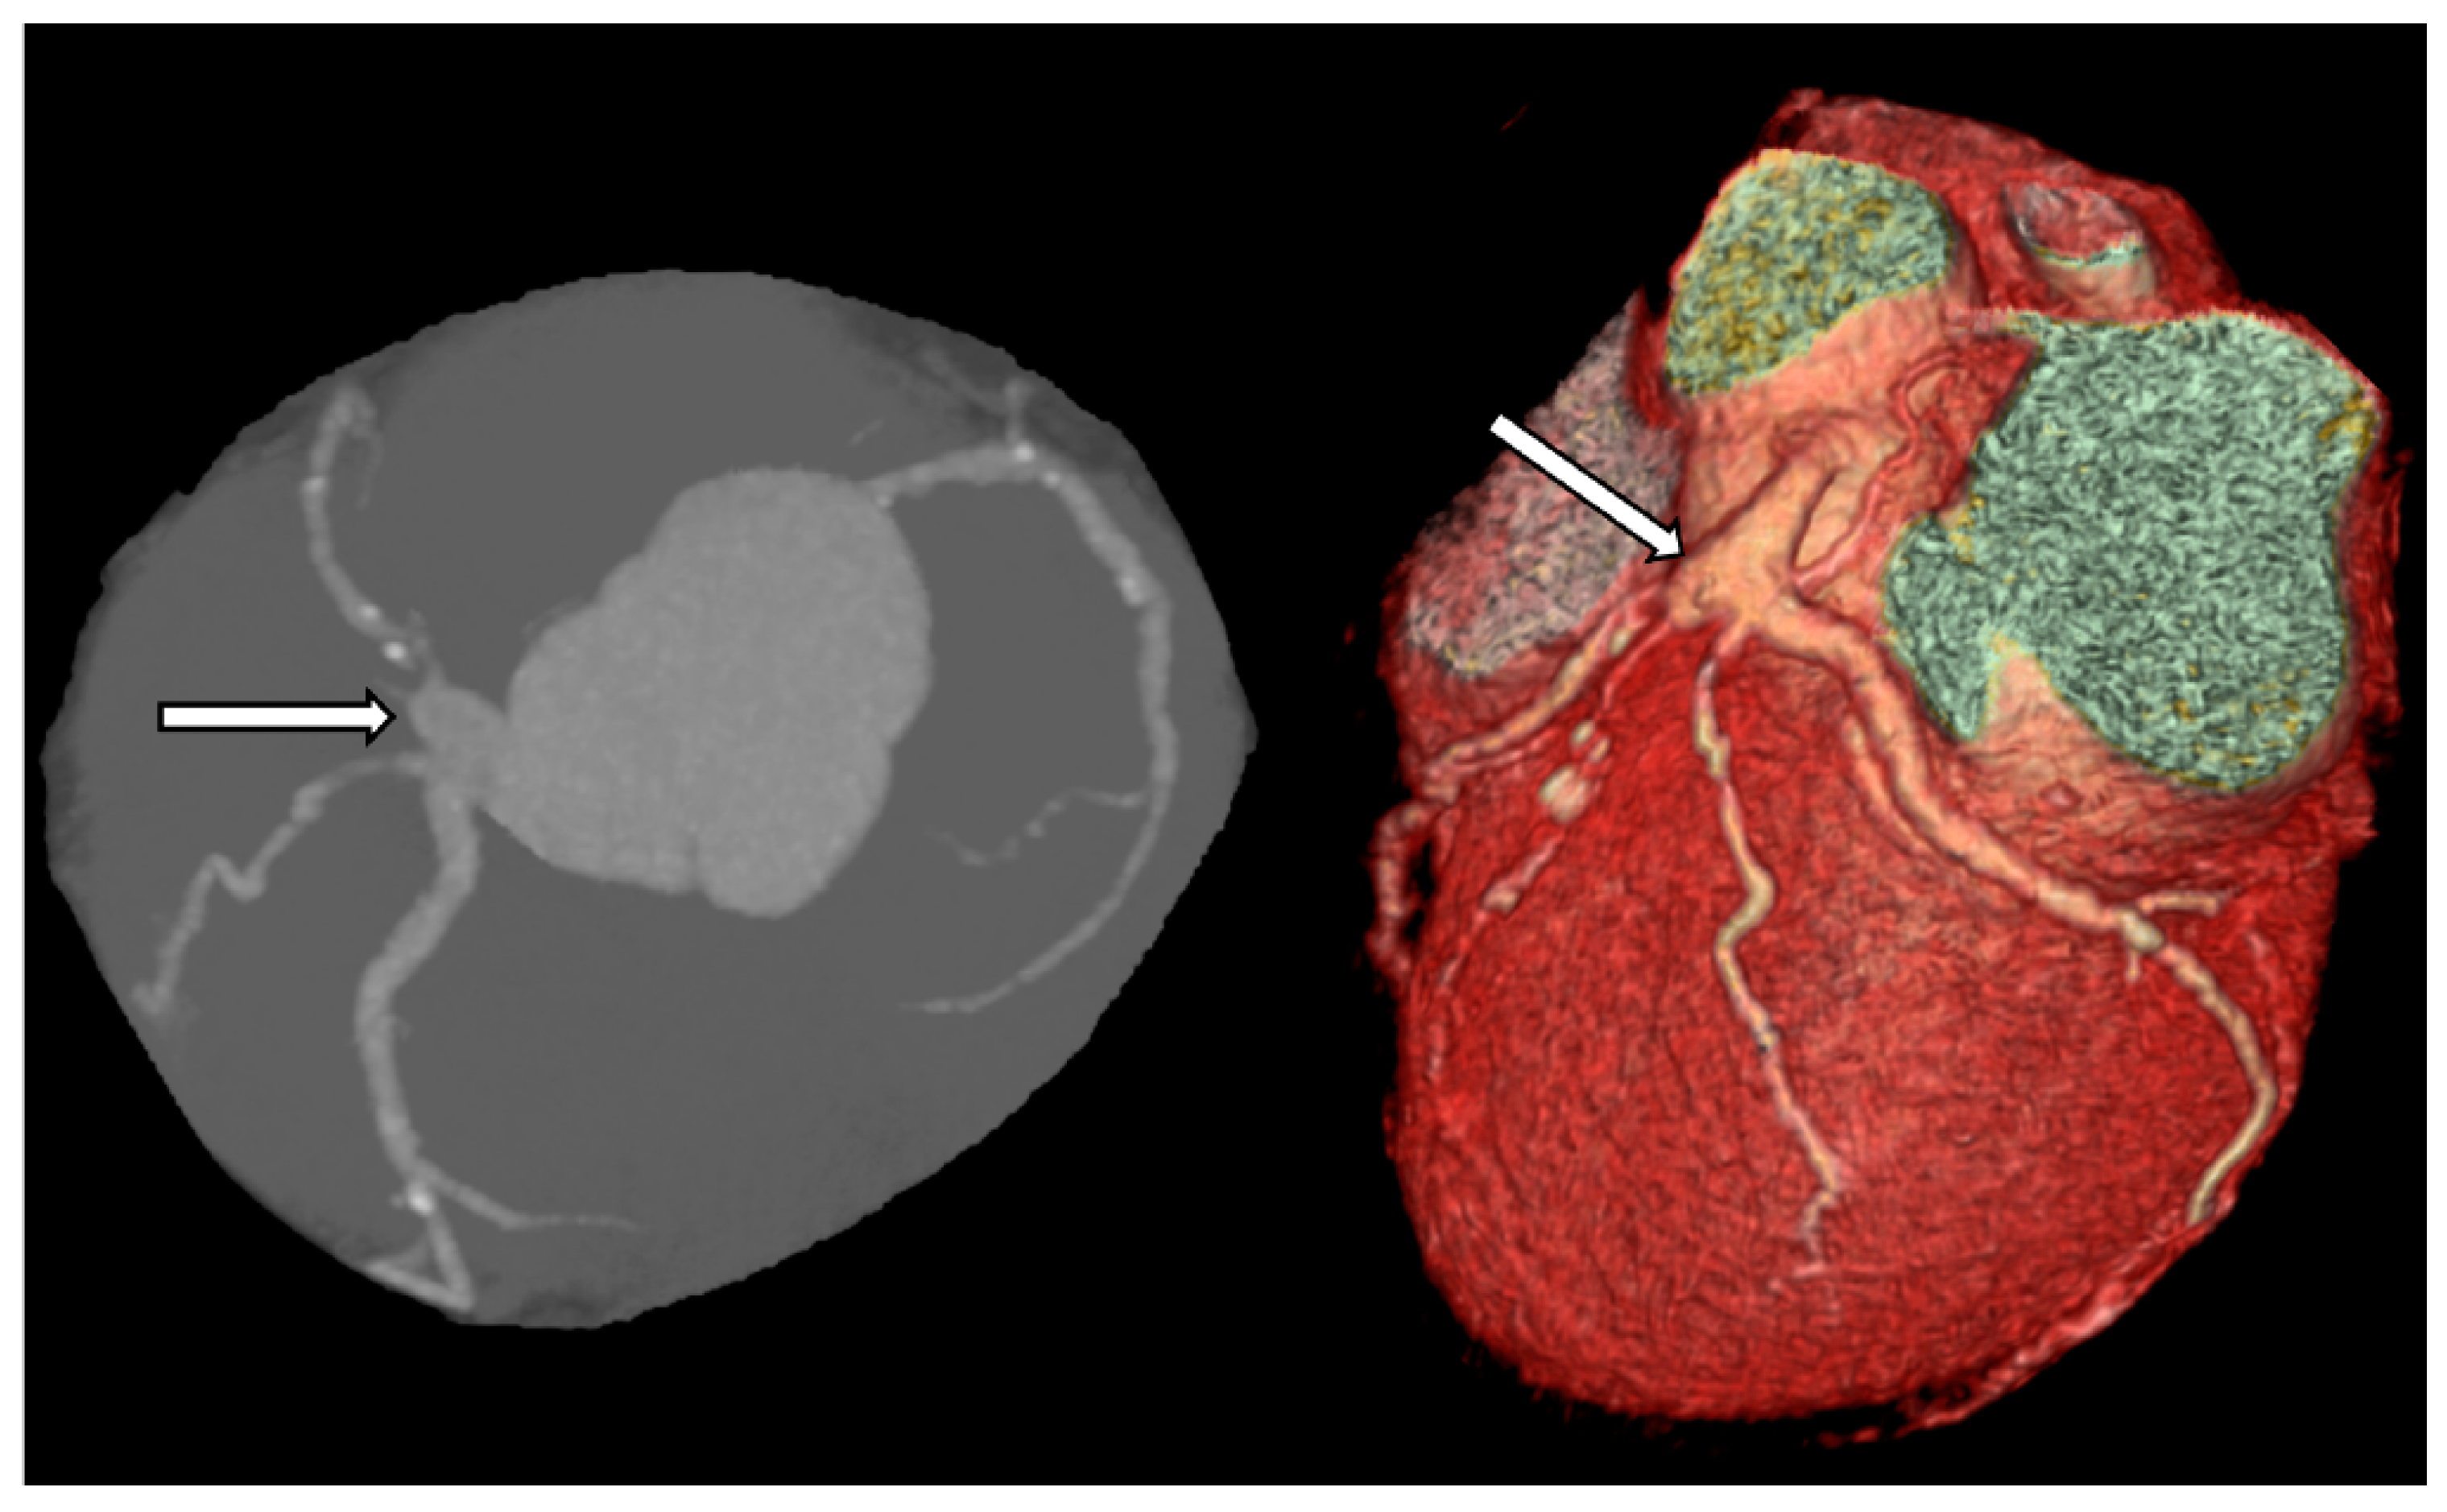

4. Diagnostics